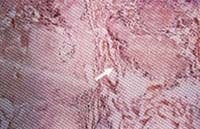

La biopsia de piel evidenció una inflamación granulomatosa con depósito de material eosinófilo amorfo rodeado por empalizada de histiocitos, presencia de células gigantes en la dermis y el panículo con linfocitos dispersos (Figura 3B).

Figura 3 B. Biopsia de piel de lesión ulcerada, en donde se observa material eosinófilo amorfo en la dermis profunda rodeado por histiocitos en empalizada (H &E 10X).

El estudio con microscopio de luz polarizada reveló la presencia de cristales de urato monosódico. El ácido úrico sérico del paciente se encontró en 10,5 mg/dl.